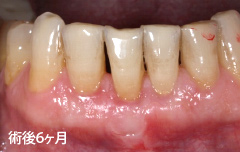

| 深い虫歯のケースでは、切除療法を行い虫歯を取り除き、健全な歯質を歯肉の上に出し、歯肉の盛り上がりを数ヶ月待ってから歯型をとります。 |

| 切除療法の目的は、しっかりと虫歯を取り除き、健全な歯質の獲得と生理的骨形態を付与することす。治療後の歯肉も、高い清掃性、長期安定性を兼ね揃え、永続性が期待できます。(一方で、歯の形態が長くなる・治癒に時間がかかりますので、切除療法と組織付着療法の術式選択は、患者様とのお話合いの上で決めて行きます。) | |||